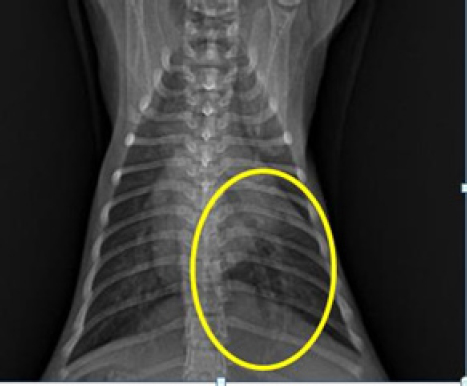

In examining the size of the heart via dorsoventral X-ray, the method used is a comparison of the width of the heart and the width between the right and left ribs and the comparison of the length of the boundaries of the right and left ribs with the heart. The measurement results in (Fig. 6) show a comparison of the length of the border of the right and left ribs with the heart RL, the length of the border between the ribs and the heart on the dexter and sinister parts is not the same (abnormal). In measuring the comparison of the width of the heart and the width between the right and left ribs, length B is greater than 2/3 A (abnormal), whereas normal is BA (Holland, 2020).

When evaluating the cardiac dimensions through dorsoventral X-ray analysis (Birsan et al., 2017), a technique employed involves assessing the heart’s width relative to the space between the right and left ribs, as well as comparing the length of the right and left rib margins concerning the heart. The findings in Figure 6 indicate a comparison between the length of the border of the right and left ribs against the heart RL. Notably, there exists an abnormality in the length of the border between the ribs and the heart on the dexter and sinister parts, as they are not of equal dimensions. According to Holland (2020) findings, aberrant results were obtained when assessing the ratio of the width of the heart to the width between the right and left ribs, with length B being greater than 2/3 A. In contrast, a normal outcome was observed when the ratio of B to A was within typical parameters.

Fig. 2. Thoracic radiograph of Hiro’s cat in a dorso ventral (DV) changes in vascular patterns with dilatation of the pulmonary arteries and veins caudals.

Fig. 6. Method of measuring the heart in the DV position (Left). Heart measurement with the VHS method of the Buchanan and Bucheler methods (Right).

During the X-ray examination, heart measurements were taken to identify any changes in the size of the heart organ. The lateral view measurements resulted in an intercostal measurement technique score of 4, with a normal range of 2.3–3.5. The height from the apex to the vertebral column was also measured compared to the carina, resulting in A being greater than 1/3 A + B and B being greater than 2/3 A + B (normal values are A < 1/3 A + B and B < 2/3 A + B). The VHS was also measured, and there was an increase in VHS results in CHF cases as mentioned in previous research in cats (Smith et al., 2004; antecedent corticosteroid administration has been noted in cats with congestive heart failure (CHFLaudhittirut et al., 2020), resulting in a score of 8 VT (the normal value is 7.5 VT). Measurements were then taken using the dorsoventral position, resulting in the heart size being different in R and L distances, with L being larger than R. The size of B was also greater than 2/3 (normally, R is equal to L, and B is less than 2/3). From these measurements, it was determined that the heart was enlarged or experiencing cardiomegaly. Cardiomegaly is the heart’s compensation for heart failure to meet the body’s circulatory needs, which can be caused by congestive heart failure (CHF), valvular heart disease, and cardiomyopathy (Triakoso, 2020).